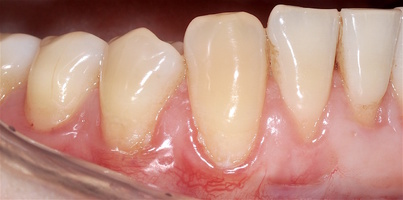

Во всех случаях применения аутотрансплантата и ТМО (dura mater) наблюдается сопоставимый положительный клинический результат по всем параметрам оценки рецессий десны (табл. 4). В случае нескольких зубов в области наиболее глубоких рецессий с наименьшими клиническими показателями имеет место сохранение класса рецессии не более первого класса (9 зубов) и глубиной не более 2 мм, 1.6 зуб — 3 мм.

В зарубежной литературе встречается также совокупный показатель эффективности лечения рецессий десны — процент закрытия корня зуба — отношение разница между конечным и исходным значениями глубины рецессии к исходному значению в процентах. Положительный результатом лечения является значение равное или более 80% [4]. Использование только показателя глубины рецессии десны для анализа эффективности лечения без учета остальных показателей (ТКД, ШКД, РРД, ЗДК) не дает полной картины результата и может быть применимо только в совокупности с другими показателями (рис. 6а-й).

Так в нашем случае процент закрытия корня зуба наблюдается больше 80% у 13 зубов. Менее 80% — у 11 зубов. Это связано с сохранением класса рецессии после лечения в области зубов с наибольшим классом рецессии и наибольшим показателем глубины рецессии. При этом средний показатель всех 24-х оперированных зубов — 83,1%. При этом среднее значение процента закрытия корня зуба для зубов с положительным результатом (более 80%) составляет 96,65%. Среднее значение для результатов менее 80% — 54,73, что связано с изменением глубины рецессий с 6 мм до 3 мм, с 4 мм до 2 мм и с 2 до 1 мм. При этом для аутотрансплантата и для ТМО результаты сопоставимы.

Через 12 месяцев (рис. 7а-г) на срезах компьютерной томограммы 11-ый и 13-ый зубы находятся в костной ткани, при этом костные пики и перегородки укрепились, объем их увеличился; вестибулярно заметен объем костной массы, предположительно компактной формации, исходя из электронной плотности участка. Этим объясняется отсутствие рецидива при лечении рецессии десны как в случае применения аутотрансплантата, также и ТМО (dura mater).